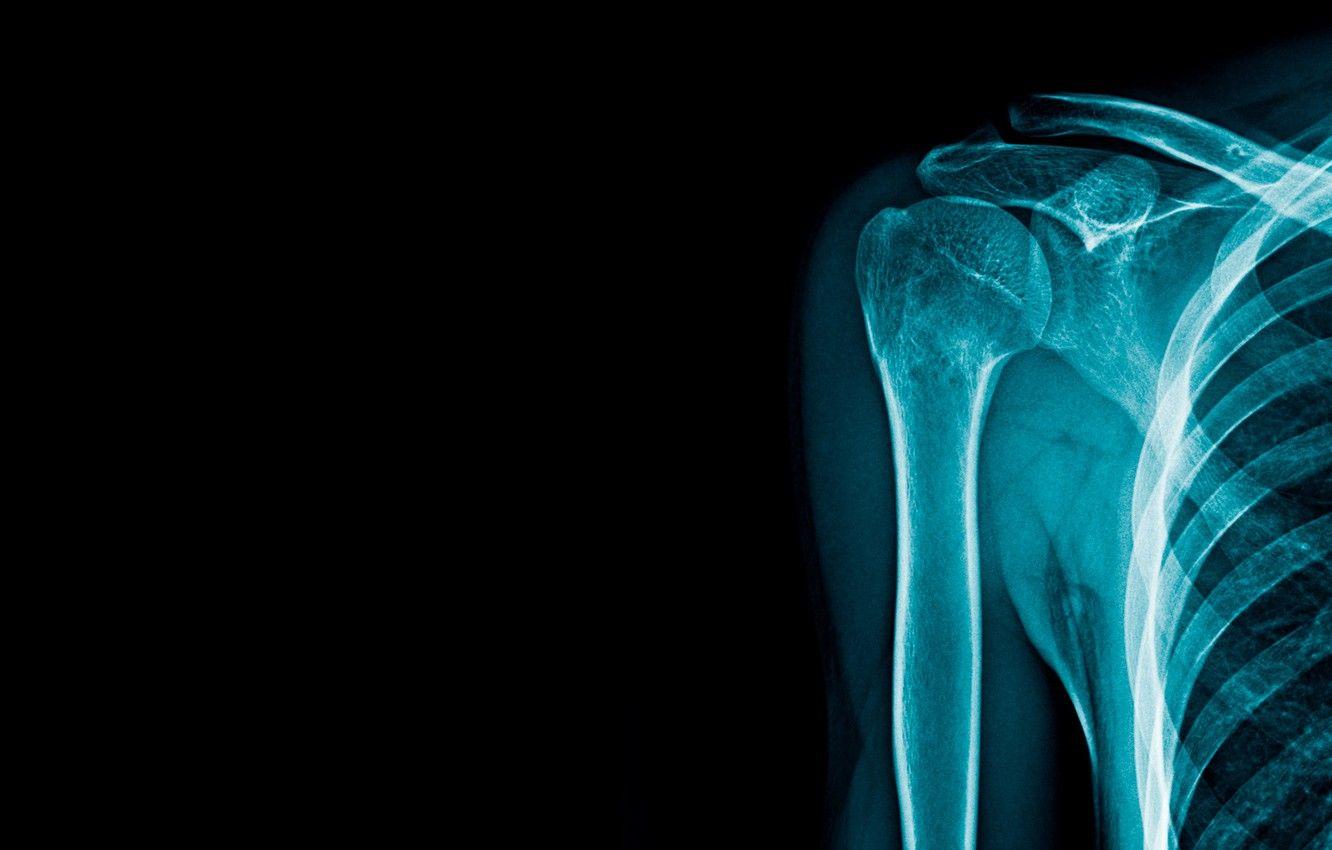

![[100+] X Ray Wallpapers | Wallpapers.com](https://wallpapers.com/images/hd/x-ray-uoe5bizemojpnhqj.jpg) wallpapers.comRadiologic Technologist Wallpapers - Top Free Radiologic Technologist

wallpapers.comRadiologic Technologist Wallpapers - Top Free Radiologic Technologist

wallpaperaccess.comradiology radiologic technologist bones wallpaperaccess

wallpaperaccess.comradiology radiologic technologist bones wallpaperaccess